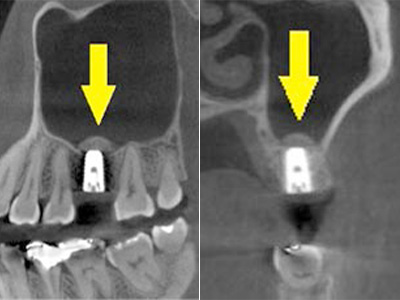

患者様ご自身の下顎前歯の下方から骨を採取して、骨がなかった部位に移植しスクリューで固定したCT画像です。

黄色矢印部分が、2つの骨片を移植して、固定したところです。 -

手術後の、別な方向からみたCT画像です。

術前に大きく吸収されていた部分に骨のブロックが移植され、骨が造成されています。

真っ白にピンのように写るのは(黄色矢印)、骨を固定した小さなスクリューです。 -